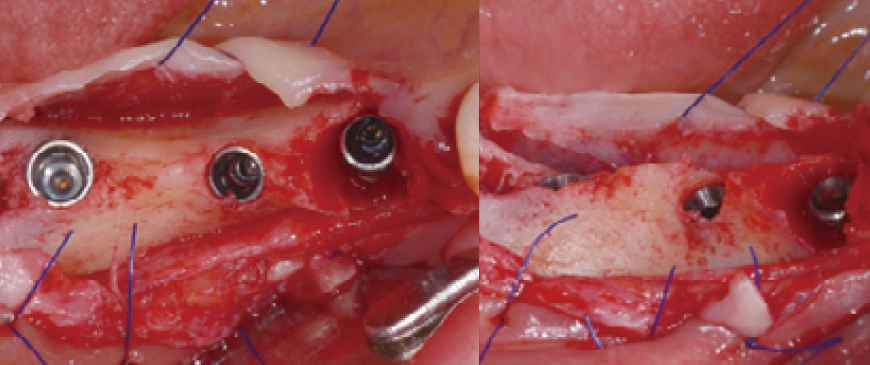

Fig 3

Upon flap elevation, it was confirmed that the first molar region also exhibited a significantly thin ridge condition.

Fig 4

In cases of thin ridges, immediate drilling can be challenging due to the risk of slippage. To improve drilling accuracy and stability, a small amount of bone can be removed at the drilling point using a rongeur or similar instrument, making the drilling process significantly easier and more controlled.